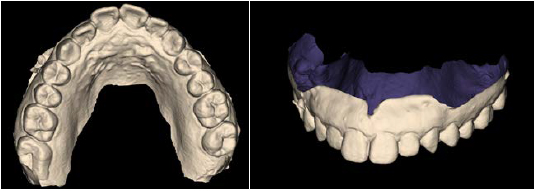

Режим сканирования модели.

Возможность сохранения исследования в STL формате для дальнейшего сочетания с CAD/CAM технологиями или создания и печати хирургического шаблона.

Экспортированные STL данные подходят лоя проектирования временных протезов, имплантатов и для ортодонтического лечения.

Модели.jpg